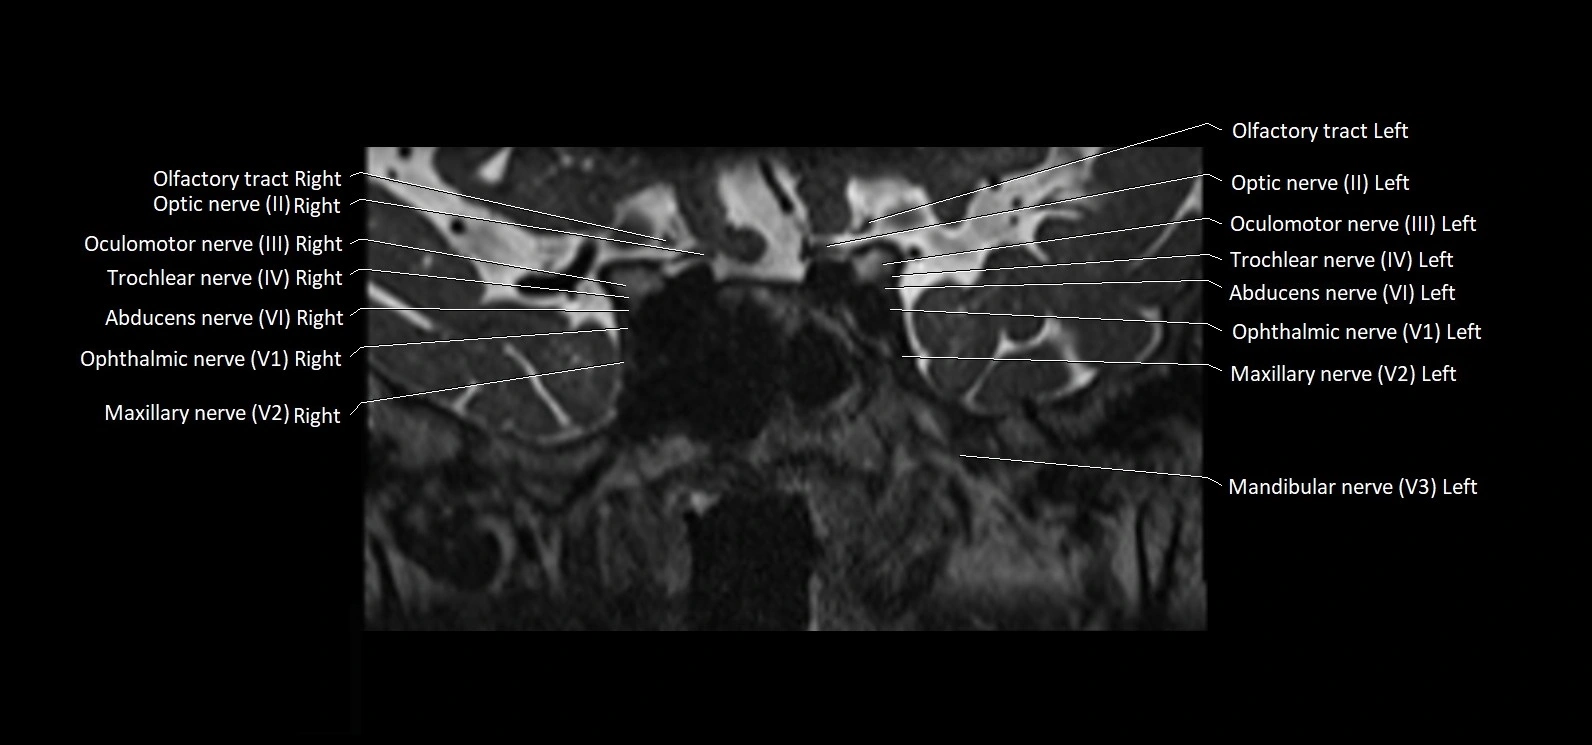

MRI Appearance

• The abducens nerve is a small, thin, linear structure

• Best visualized on high-resolution T2-weighted 3D MRI sequences (e.g., FIESTA or CISS)

• Seen as a hypointense (dark) line running from the brainstem at the pontomedullary junction, traversing the prepontine cistern, and entering Dorello’s canal under the petrosphenoidal ligament, then into the cavernous sinus, and finally the orbit

• May be challenging to visualize in standard MRI due to its small size

• Pathology may be inferred by absence, displacement, or enhancement of the nerve